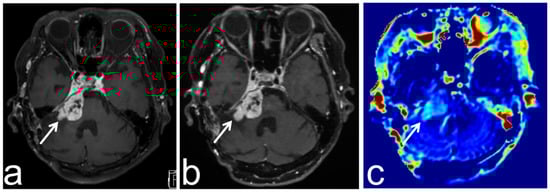

6. APT-CEST Imaging of Meningioma

7. APT-CEST Imaging of Benign Lesion